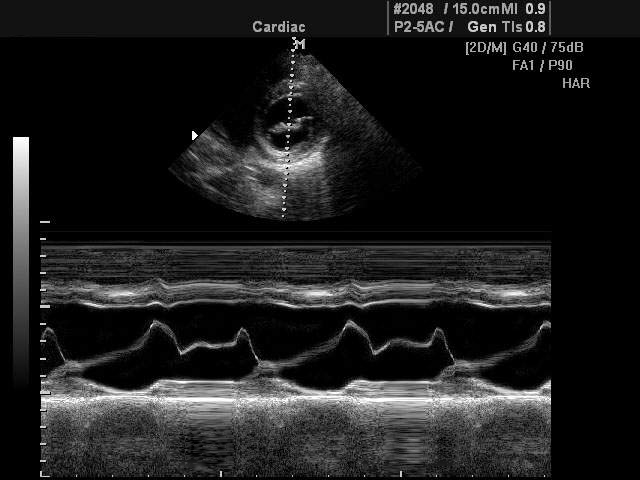

M-режим разработан специально для исследований подвижных структур в реальном времени (от английского motion - движение). Наибольшее применение М-режим нашел в исследовании структур сердца (оценка размеров, сократительной функции сердца, работа клапанного аппарата и т.д.).

При помощи M-эхограммы специалист может количественно оценивать геометрическое смещение подвижных структур и измерять их изменение относительно взаимного положения (просвет в клапанах сердца, изменение размера желудочка и прочее). M-режим зачастую используется вместе с B-режимом (англ. brightness - яркость), во время диагностики врач в B-режиме выбирает необходимый ракурс наблюдения, а затем с помощью курсорной линии на B-эхограмме выбирает направление оси ультразвукового луча для M-режима. Положение датчика фиксируется рукой доктора, после чего включается M-режим.

В М-режиме зондирование периодически повторятся в одном и том же направлении акустического луча. При формировании М-эхограммы в каждом зондировании амплитудная информация об эхо-сигналах с различных глубин отображается в виде отметок различной яркости вдоль вертикальной линии на экране (акустической строки). Следующему зондированию соответствует своя линия, расположенная правее предыдущей, в процессе перемещения столбца с каждым новым зондированием формируется двухмерная М-эхограмма. Положение яркостных отметок по вертикали пропорционально глубине отражающей структуры, например, сердечного клапана.